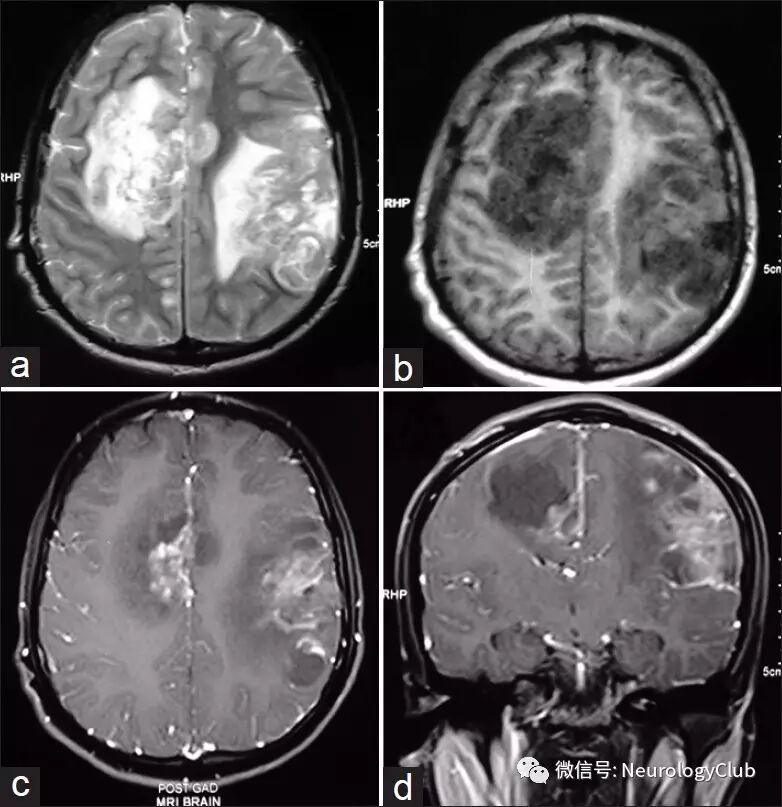

18岁男性,表现为进行性加重的左顶部疼痛逐渐发展为全头部疼痛27天,伴有恶心呕吐,右侧肢体渐进性轻偏瘫5天。无畏寒发热,无免疫缺陷及免疫抑制治疗的既往史。查体可见颈项强直,右侧轻偏瘫。脑脊液化验提示糖71mg/dL,蛋白132mg/dL,有核细胞20/dL(均为淋巴细胞),抗酸染色及细菌涂片阴性。CT及MR可见颅内多发病变伴强化(图1-2)。余常规实验室及影像学检查无殊。

(图2:T2WI[a],T1WI[b]和T1增强[c-d]可见多发病变,最大者位于左侧额顶叶,呈肿瘤样,伴散布的出血和线状脑回样强化)

中枢神经系统阿米巴病是一种由自由生活阿米巴感染所致的罕见疾病,大致可分为肉芽肿性阿米巴脑炎(granulomatous amebic encephalitis,GAE)和原发性阿米巴脑膜脑炎(primary amebic meningoencephalitis,PAM)。GAE为棘阿米巴属和巴拉姆希属(如狒狒巴拉姆希阿米巴亚)急性-慢性感染所致,不同于PAM,后者由福氏耐格里属阿米巴引起,急性起病,快速进展,患者在48-72h内死亡。本病潜伏期尚不清楚,推测在10天以上。患者年龄常为10-30岁,男女比例大于10:1。病理学上,可见局灶性脑炎或微脓肿形成以及软脑膜炎。GAE可有较长时间的局灶性神经功能缺失症状。影像学上可呈多灶脑实质病变,坏死,病灶内出血,假瘤样表现和软脑膜炎。肿瘤样病灶(假瘤型)常有线状浅表脑回样强化,有助于诊断。可能代表了炎性脑膜和其下皮层的共同强化。阿米巴通过软脑膜血管进入脑实质可引起微脓肿。多灶型病变可为T2高信号及环形强化,好发于间脑、脑干和后颅窝结构。早期诊断并手术切除肉芽肿性肿瘤样病灶,再联合化疗,如两性霉素B或克霉唑,是提高生存率的最佳选择。即便如此,本病预后仍然很糟糕。